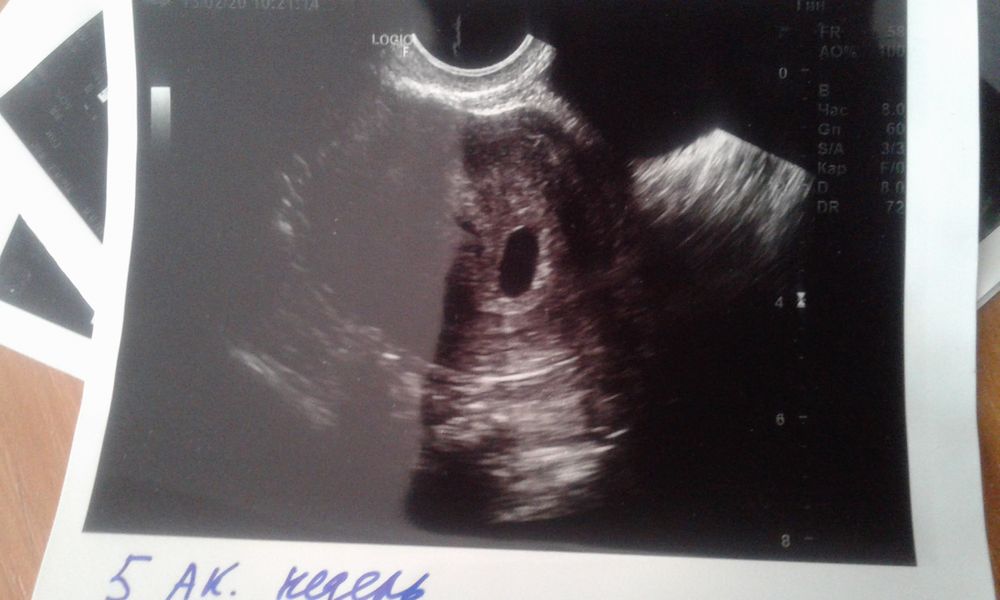

Изображение У меня такое было